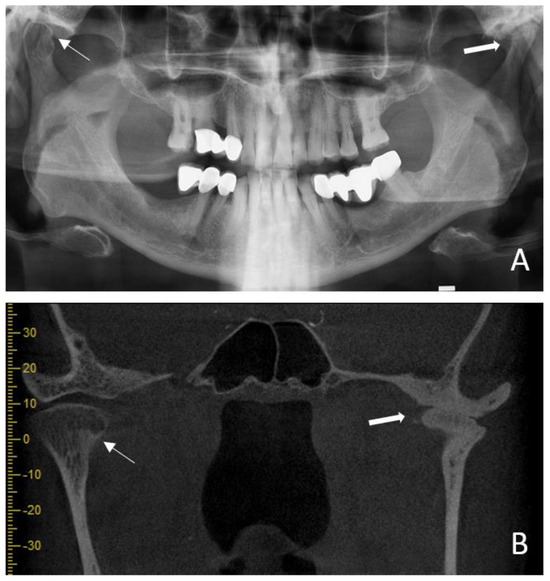

| Condylar erosion-1 | 69 (53.1%) | 41 (31.5%) | 110 (42.3%) | <0.001 | 0.97 | <0.001 |

| Condylar erosion-2 | 69 (53.1%) | 38 (29.2%) | 107 (41.2%) | <0.001 | ||

| Condylar flattening-1 | 49 (37.7%) | 24 (18.5%) | 73 (28.1%) | 0.001 | 0.98 | <0.001 |

| Condylar flattening-2 | 48 (36.9%) | 23 (17.7%) | 71 (27.3%) | 0.001 | ||

| Subcortical sclerosis-1 | 54 (41.5%) | 17 (13.1%) | 71 (27.3%) | <0.001 | 0.99 | <0.001 |

| Subcortical sclerosis-2 | 54 (41.5%) | 18 (13.8%) | 72 (27.7%) | <0.001 | ||

| Osteophyte-1 | 50 (38.5%) | 22 (16.9%) | 72 (27.7%) | <0.001 | 0.99 | <0.001 |

| Osteophyte-2 | 50 (38.5%) | 21 (16.2%) | 71 (27.3%) | <0.001 | ||

| Subcortical cyst-1 | 44 (33.8%) | 17 (13.1%) | 61 (23.5%) | <0.001 | 1 | <0.001 |

| Subcortical cyst-2 | 44 (33.8%) | 17 (13.1%) | 61 (23.5%) | <0.001 | ||

| Articular eminence resorption-1 | 21 (16.2%) | 4 (3.1%) | 25 (9.6%) | 0.001 | 1 | <0.001 |

| Articular eminence resorption-2 | 21 (16.2%) | 4 (3.1%) | 25 (9.6%) | 0.001 | ||

| Ankylosis-1 | 5 (3.8%) | 3 (2.3%) | 8 (3.1%) | 0.722 | 1 | <0.001 |

| Ankylosis-2 | 5 (3.8%) | 3 (2.3%) | 8 (3.1%) | 0.722 | ||

| Joint space narrowing-1 | 25 (19.2%) | 15 (11.5%) | 40 (15.4%) | 0.122 | 0.98 | <0.001 |

| Joint space narrowing-2 | 25 (19.2%) | 14 (10.8%) | 39 (15%) | 0.082 | ||